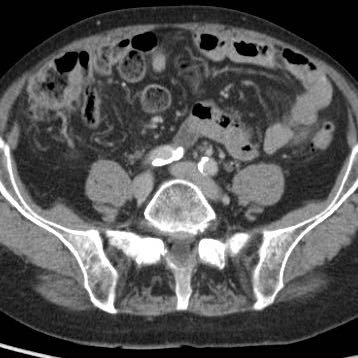

Dấu hiệu gián tiếp của viêm ruột thừa

Ở những bệnh nhân không thể quan sát được ruột thừa trên siêu âm và cũng không tìm thấy bệnh lý thay thế nào, các dấu hiệu gián tiếp của viêm ruột thừa có thể hữu ích.

CT xác nhận tình trạng giải phẫu.